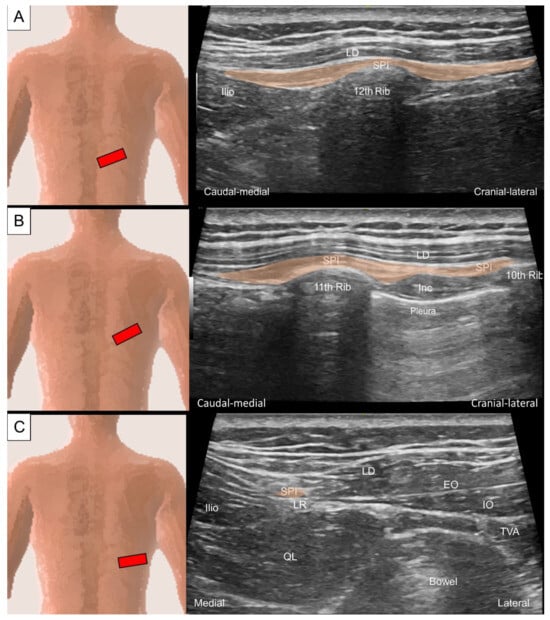

5. Intrinsic Muscles of the Thoracic and Lumbar Regions

5.1. Iliocostalis Thoracis, Longissimus Thoracis, Semispinalis Thoracis, and Thoracic Multifidus

5.1.1. Anatomy

5.1.2. Sonographic Scanning

5.1.3. Clinical Relevance